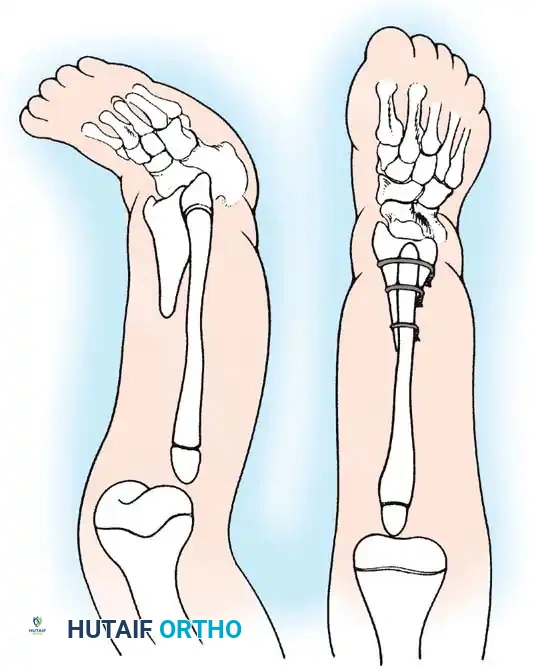

In Type 1B and Type 2 deformities, a functional knee joint exists (or will develop from the anlage), and knee disarticulation is contraindicated provided the quadriceps mechanism is functional.

The treatment of choice is a proximal tibiofibular synostosis combined with a Syme amputation or complex distal reconstruction. Creating a synostosis between the fibula and the proximal tibia creates a uniform, in-line, weight-bearing mechanical axis. If the fibula is not surgically transferred and fused to the tibia, a peculiar, curved, hypertrophied fibula develops, causing a severe secondary deformity. Fusing the fibula underneath the tibia encourages its hypertrophy in a mechanically advantageous alignment.

Proximal Tibiofibular Synostosis

For Type 1B and Type 2 tibial hemimelia, centralizing the mechanical axis is critical. The fibula must be brought under the mechanical axis of the femur or the existing proximal tibial anlage.

Technique Overview:

1. A lateral or anterolateral approach is utilized to expose the proximal fibula and the tibial anlage.

2. The proximal fibula is carefully osteotomized or mobilized, taking extreme care to protect the common peroneal nerve, which often has an anomalous course in these patients.

3. The cartilaginous tibial anlage is split or prepared to receive the proximal fibula.

4. The fibula is centralized beneath the tibia/anlage and fixed using smooth Kirschner wires or a small fragment plate, depending on the child's age and bone quality.

5. Bone graft (autograft or allograft) is packed around the synostosis site to promote rapid union.

By fusing the fibula to the tibia, the surgeon prevents the progressive lateral bowing and hypertrophy of the fibula that inevitably occurs if it is left in its native, eccentric position. This synostosis provides a robust, centralized bony column that can later be lengthened or fitted with a prosthesis following a distal Syme amputation.